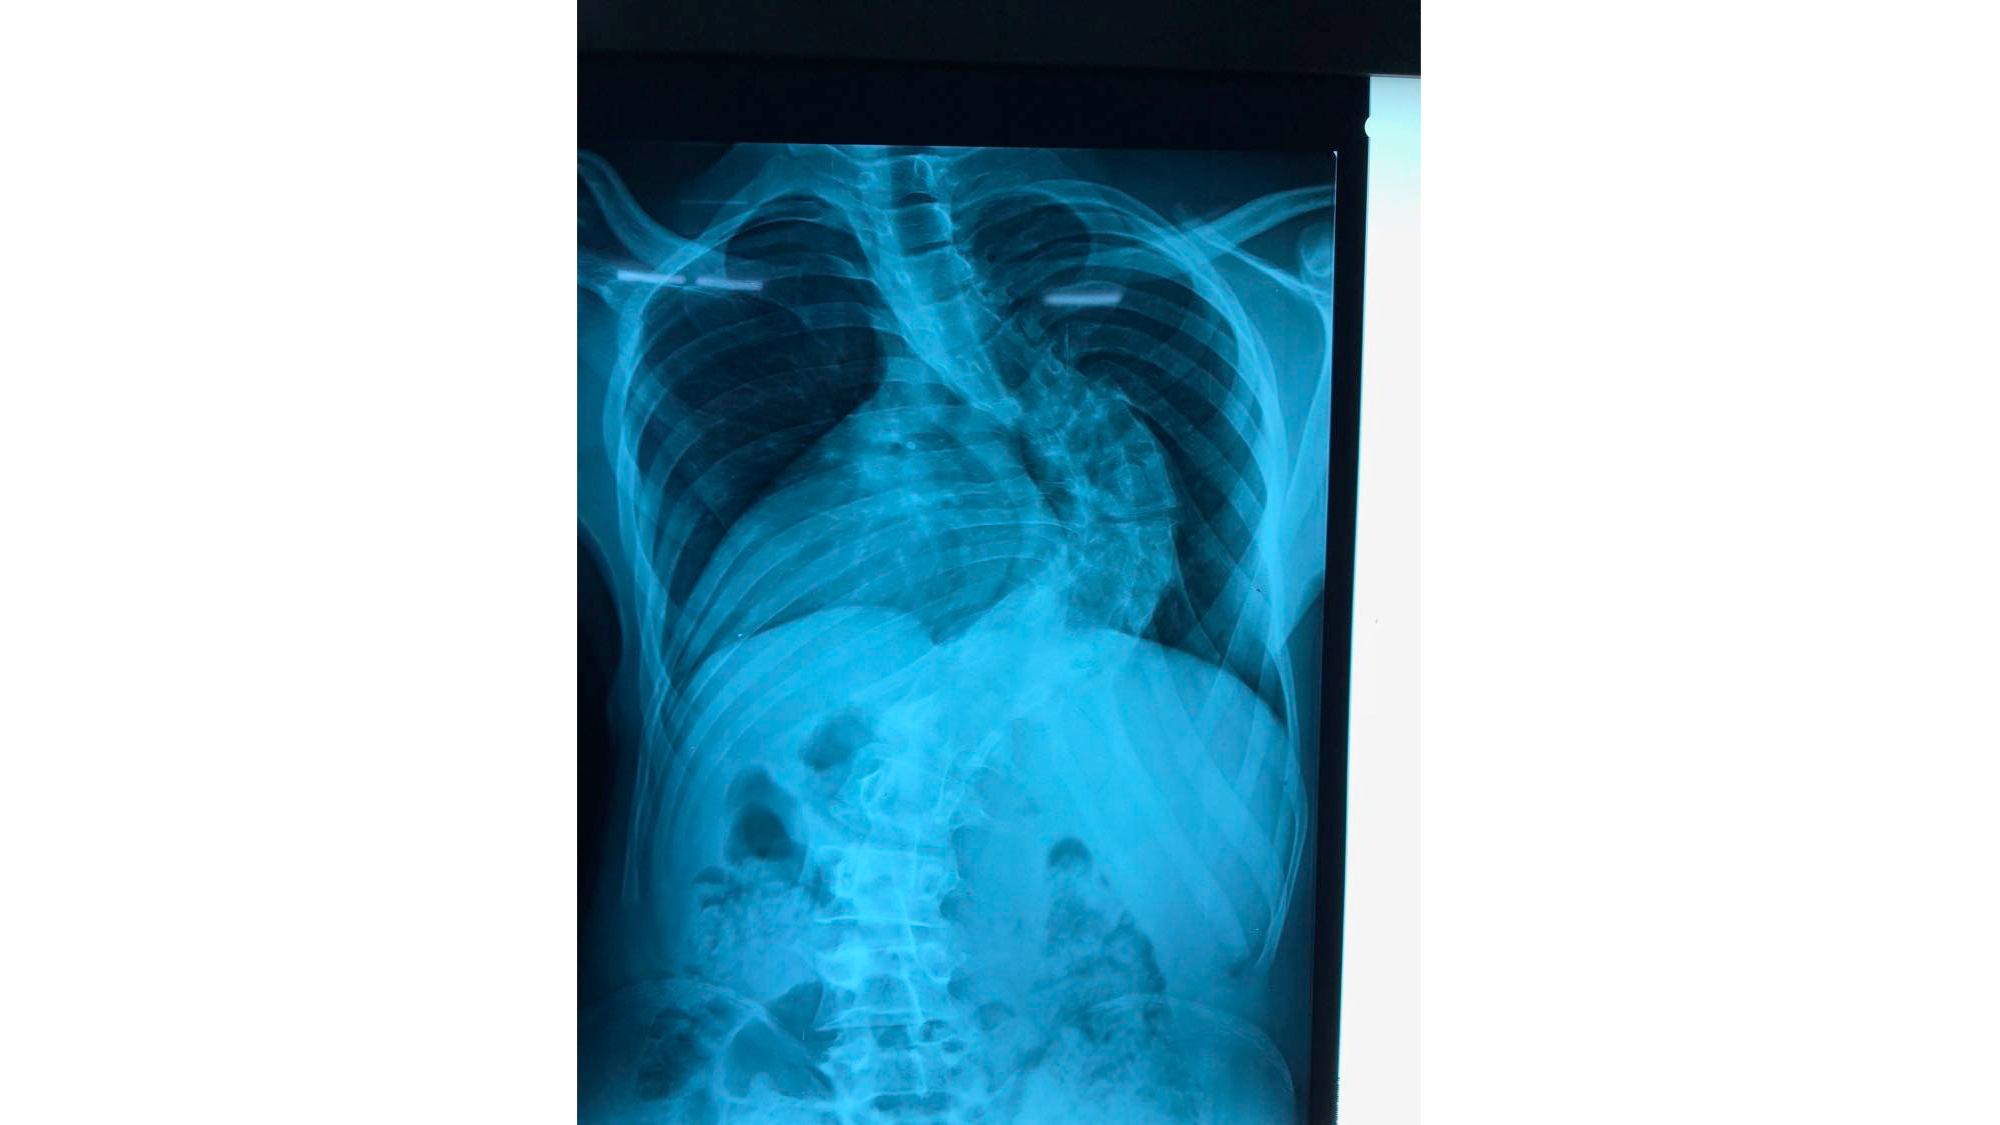

I was also able to meet the first two spine surgery fellows at AaBET. They are both neurosurgeons. The plan after next year is to alternate orthopedic with neurosurgery spine fellows. In addition to their teaching at AaBET, they are mentored by Dr Fasil Mesfin of Univeristy of Missouri, with whom they have weekly cases conferences. They were excited to show me two massive spine tumors they just operated on, one a giant, dumbbell shaped neurofibroma of the lower thoracic spine with bone involvement and preoperative paraparesis; the other a huge aneurysmal bone cyst of posterior lumbar element. Both needed pedicle screw instrumentation and big exposures. I am not a spine surgeon but the operative photos and postop xrays were very impressive.